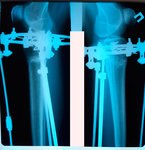

Дата операции - 04.04.2019г.

Дата снятия аппаратов - 02.07.2019г.

Срок сращения - 89 дней.